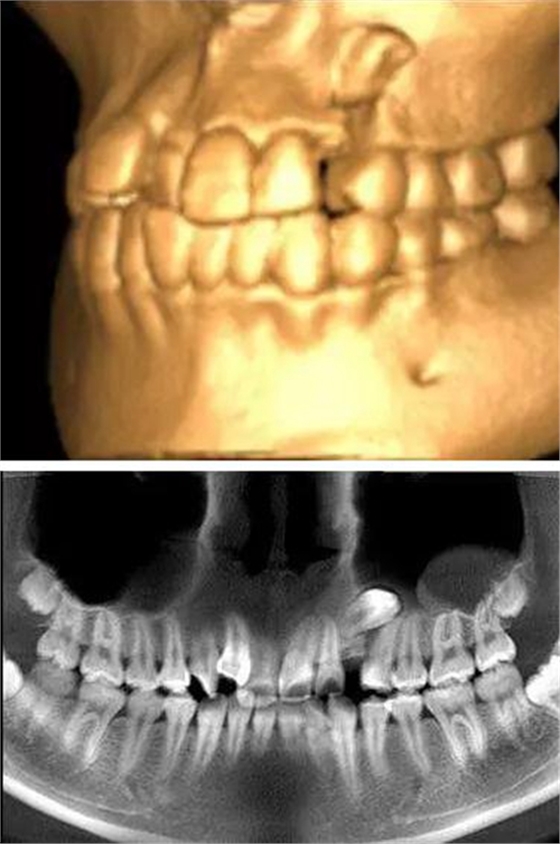

本案:患兒,女,14歲,因牙齒矯正來院,檢查見83滯留,43未見萌出,拍片發(fā)現(xiàn):43埋伏阻生于31、41、42根尖下方,按照正畸診療計劃,擬行43拔除術。

口腔牙列照片

全景片

CBCT顯示